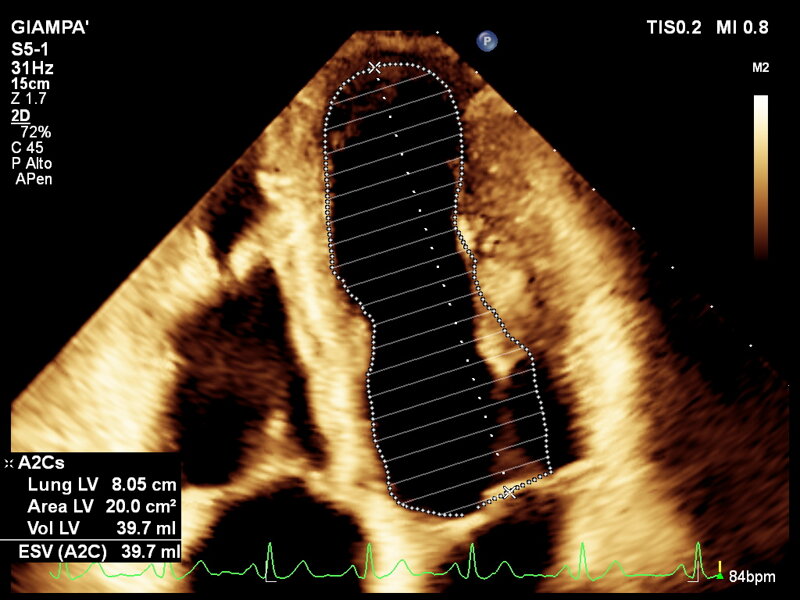

L’ecocardiografia è una metodica con cui si studiano il cuore e il flusso del sangue attraverso le valvole per mezzo degli ultrasuoni. permette di ottenere informazioni sulla contrattilità del cuore, sulla morfologia delle sue valvole e sul flusso del sangue nelle sue cavità, sia a riposo che dopo l’esercizio fisico